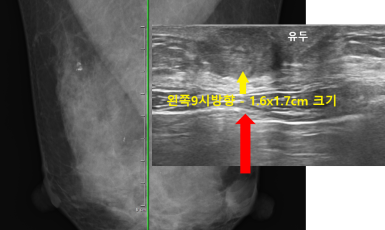

280번째 유방암 진단사례 (2020년2월4일) 몇년전부터 왼쪽 가슴에 단단한 멍울이 생겼으나 그냥 지내다 시간이 지나면서 점점 커지기 시작하였고 통증도 같이 동반되어 진..

작성자 레이디유 작성일 02-12 조회 13